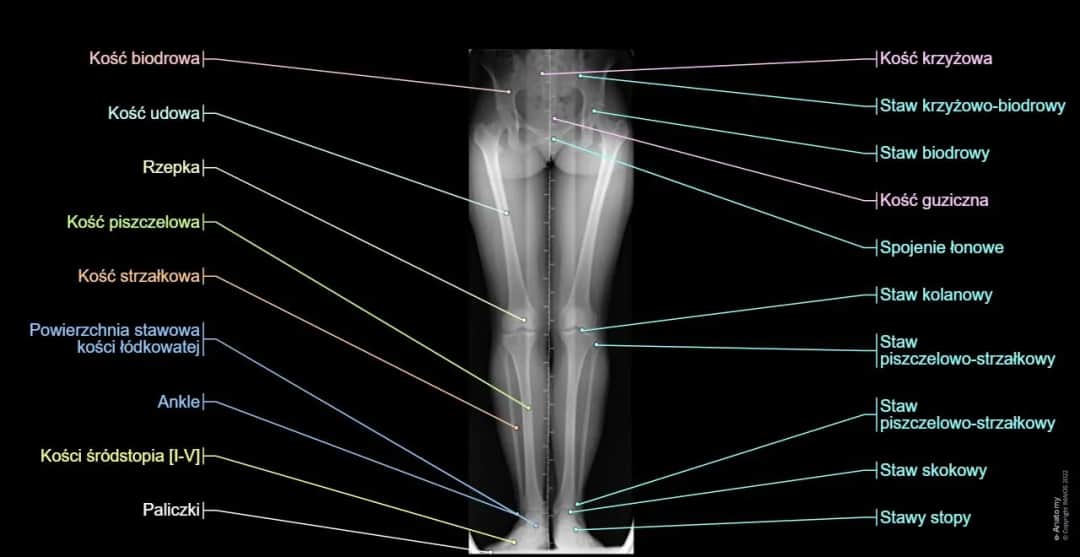

Poznaj elewację kończyny dolnej - skuteczną technikę rehabilitacji nóg. Dowiedz się, jak unoszenie nogi pomaga w leczeniu urazów i poprawie funkcji kończyn dolnych.